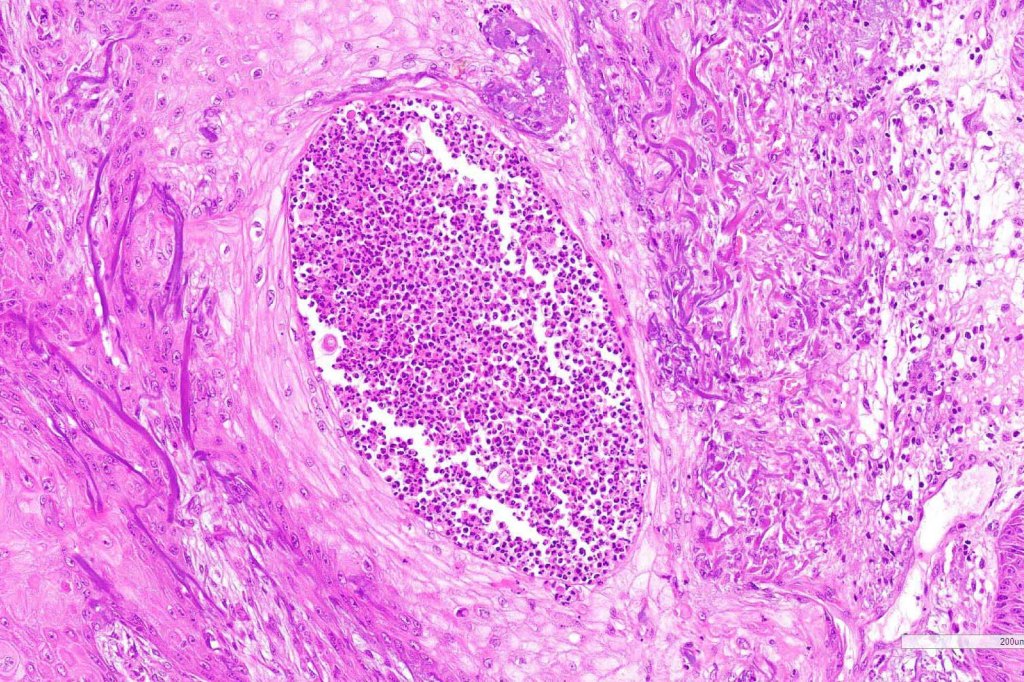

. Exceptionally, perineural infiltration and vascular involvement has been documented. If present, this should be viewed with concern as risk of recurrence or metastatic spread is significant

Below is a fascinating case shared on McKee Derm by Dr. James Simpson. There is an obvious keratoacanthoma but at the edge of the lesion there is marked atypia with nuclear enlargement and pleomorphism. This is also evident in the adjacent epidermis and in the deeper nests.